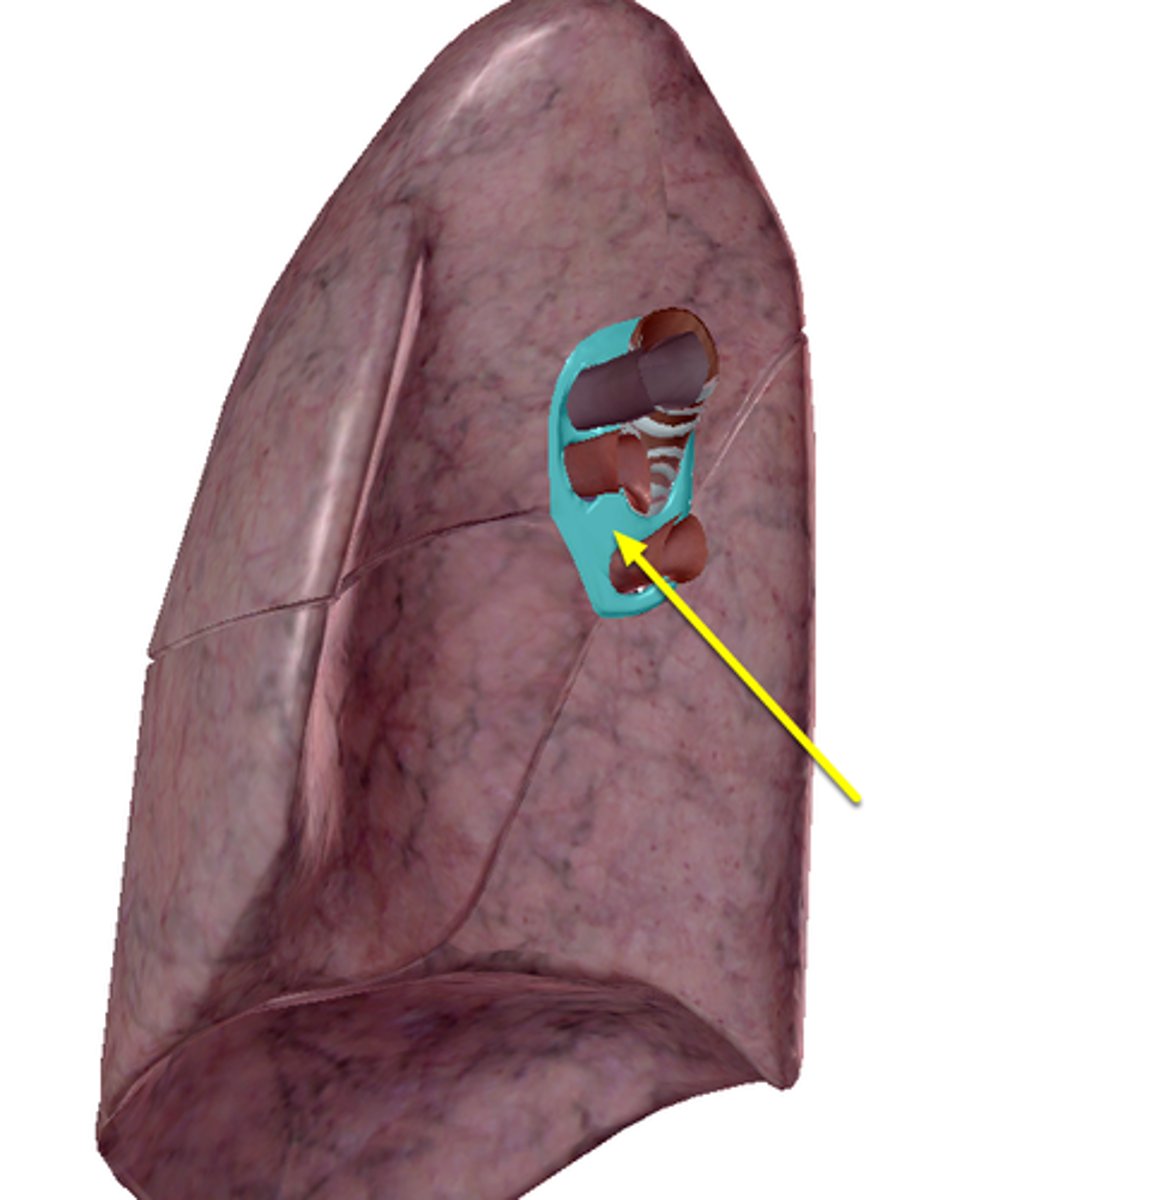

New cards

hila (singular= hilum)

place where bronchi/vessels enter lungs

<p>place where bronchi/vessels enter lungs</p>